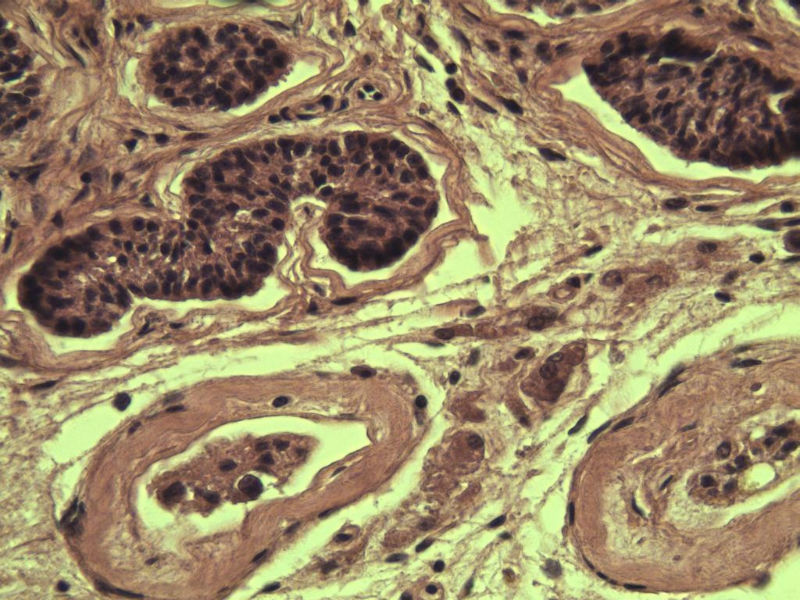

男 27岁 腹腔隐睾 5*3*2 cm, 切面灰红灰黄、实性、质中,请各位老师看看,是精原细胞瘤吗?感觉不像.腹腔隐睾图1

典型的精原细胞瘤,隐睾易恶变